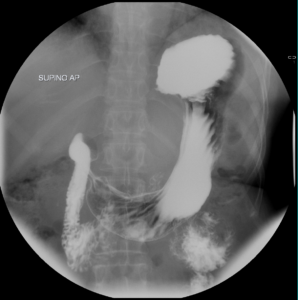

Tránsito EGD